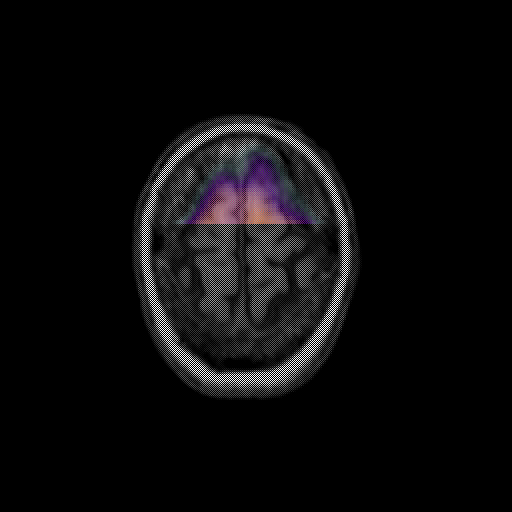

overlay: Slice 47

Slice 47

MRCBFCBF with

T1PDT2T1PDT2